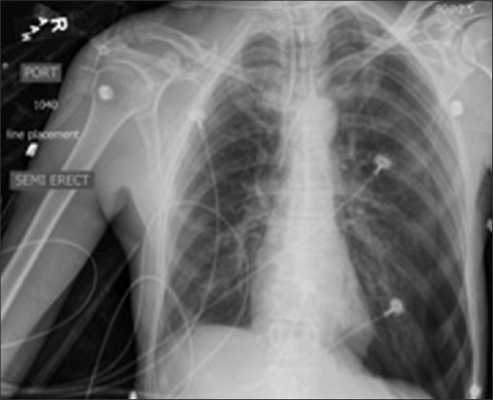

Рентгенологический контроль положения центрального катетера

После катетеризации внутренней яремной или подключичной вены необходимо произвести рентгенографию органов грудной клетки для подтверждения правильного расположения катетера и исключения пневмоторакса. Если больному проводится ИВЛ - рентгенография проводится сразу после катетеризации. При самостоятельном дыхании больного - через 3-4 часа. При признаках гемоторакса, пневмоторакса - рентгенография проводится немедленно.

Определение правильного положения дистального конца катетера на ретгенограмме

На рентгенограмме грудной клетки в передней проекции у взрослых конец катетера должен располагаться не более чем на 2 см ниже линии, соединяющей нижние концы ключицы. Эта линия разделяет верхнюю полую вену на два участка, расположенных ниже верхней границы перикарда и выше нее. Если катетер вводят в нижнюю полую вену, его конец должен располагаться ниже уровня диафрагмы.

Катетер вводят до уровня соединения 2 ребра с грудиной, что соответствует впадению полой вены в правое предсердие. После установки ЦВК рекомендуется сделать рентгенограмму грудной полости, чтобы исключить пневмоторакс на стороне пункции и уточнить расположение кончика катетера в верхней полой вене.